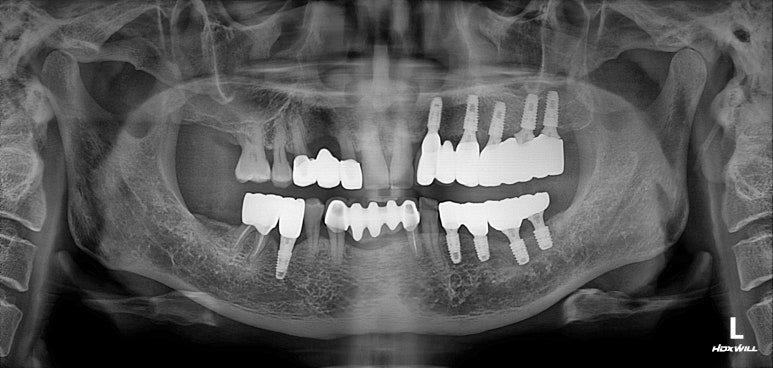

치과용 파노라마 엑스레이입니다.

임플란트가 무려 9개나 되어있네요! 여기에서 앞니 임플란트의 명백한 단점을 확인할 수 있습니다.

보이시나요? 바로 임플란트 크라운이 너~무 길다는 것.

잇몸질환 (만성 치주염)이 심하신 분들의 경우 잇몸뼈의 상실이 심해 결국 임플란트를 '깊게' 심게 됩니다.

결과적으로 치아 길이가 너~무 길어보여 결국 음식도 많이 끼고 비심미적인 (보기 안 좋은) 결과를 낳는다는 것...

사실 어쩔 수 없이 임플란트를 해야만 하는 상황이긴 하나, 잇몸뼈 염증이 심했을 땐 저렇게 어색한 임플란트 머리를 피할 수가 없습니다...

보이시는 것처럼 엄청나게 깊이 임플란트를 심어내고 결국 머리가 엄청 길어져버린 임플란트를 만들어드리게 된단 말이죠...

앞니 지르코니아 브릿지 접착 후 치과용 파노라마 사진입니다.

잘 보시면, 송곳니가 있었던 자리가 엑스레이 상에서 꽤나 어둡게 보이는 것을 확인하실 수 있으실텐데요,

실제로 CT를 찍어보면 아마 남아있는 잇몸뼈가 너무 적어 임플란트 수술에 상당히 곤란할 모양일 것입니다.

치료의 방향을 결정함에 있어서 경험을 통해 과정과 결과를 예상하고 보다 유리한 치료방법을 선택한 예임을 확인할 수 있었습니다.

이번 환자분 같은 경우 위턱의 양쪽 송곳니가 한쪽은 앞니 지르코니아 브릿지로, 한쪽은 임플란트 브릿지로 치료가 된 특이한 상황이었습니다.

무리해서 앞니에 임플란트를 수술하는 경우 (이번 경우는 어쩔 수 없었지만) 보시는 바와 같이 매우 긴 치아길이를 가진 보철물로 제작되게 되고, 장점보다는 단점이 많은 결과를 낳습니다.